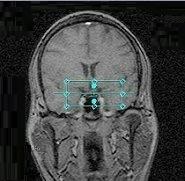

Figure 1. CSI PRESS ROI